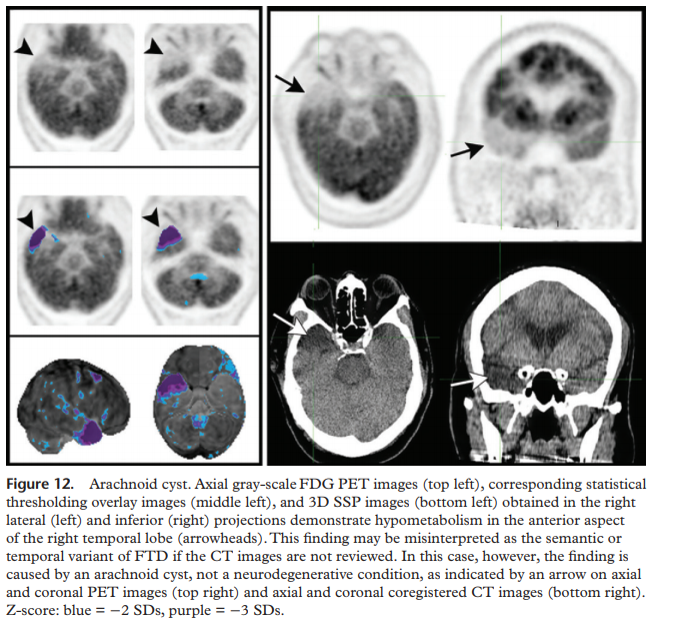

If the frontal lobe or internal capsule is involved, hypometabolism in the contralateral cerebellum may be seen due to crossed cerebrocerebellar diaschisis